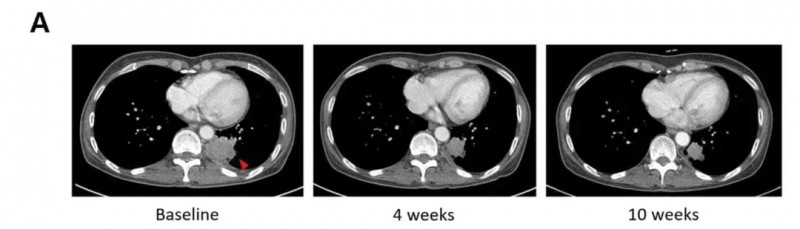

值得一提的是,其中一位腺癌患者在对吉非替尼产生耐药性后,接受SNKO1联合西妥昔单抗/吉西他滨/卡铂作为二线治疗,影像学检查显示,治疗后该患者病灶显著缩小(详见下图)。

▲图源“BMJ”,版权归原作者所有,如无意中侵犯了知识产权,请联系我们删除

另一例患者,在左上肺叶切除术2年后腺癌复发(活检证实),在先前的吉非替尼和奥西替尼治疗失败后,接受SNKO1联合西妥昔单抗/吉西他滨/卡铂作为三线治疗。影像学检查示,治疗后病灶明显缩小(详见下图)。